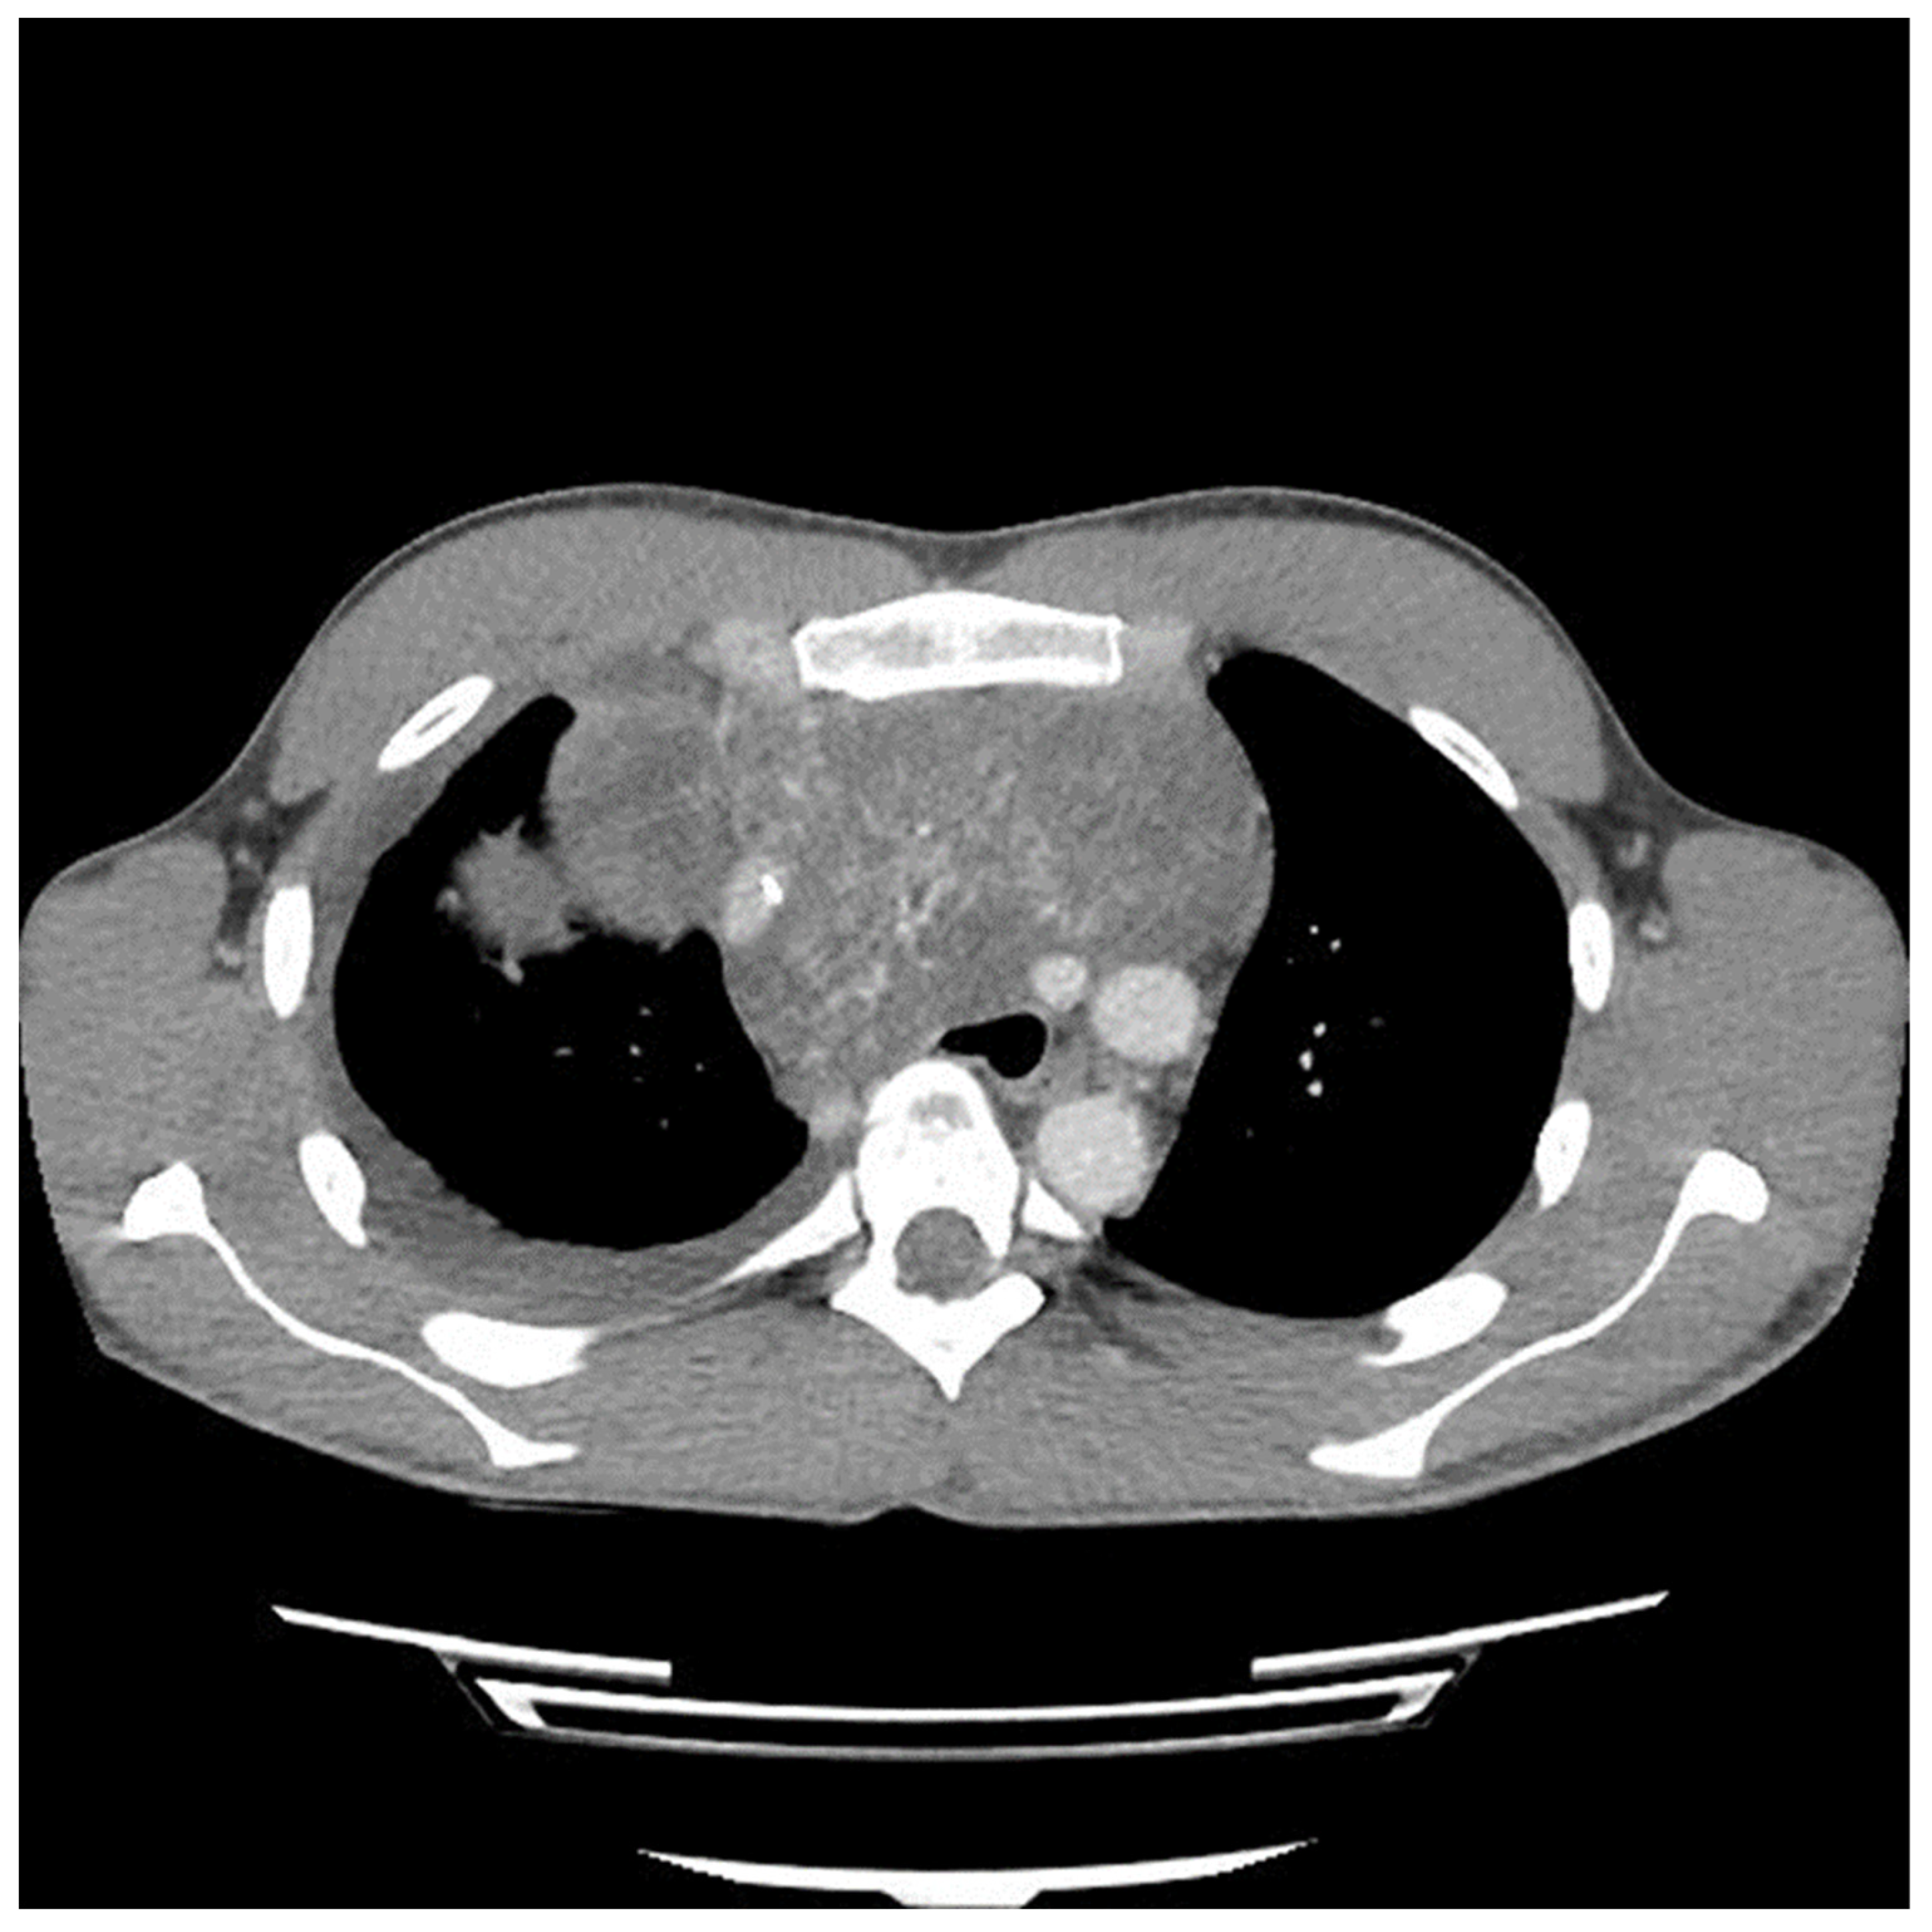

A sternotomy was performed using an oscillating saw. A plane was developed between the pericardial fat and pericardium at the level of the inferior vena cava and carried towards the left side of the tumor. Entering the left pleural space allowed release of the tumor from its left lateral attachments and identification of the left phrenic nerve. Fortunately, despite the preoperative CT (Figure 2 and Figure 3) suggesting encasement of the left subclavian artery, distracting the tumor to the right revealed it could be unwrapped and peeled off this vessel, allowing perseveration of it.

Figure 3.

Computed tomography (CT) scan image of mediastinal mass after two cycles of chemotherapy showing encasement of left subclavian artery.

The preoperative CT (Figure 1, Figure 2 and Figure 3) identified the involvement of three critical structures: (1) left subclavian artery, (2) right hilum of the lung and (3) SVC. Interestingly, only the encasement of the SVC was confirmed at the time of the surgery. The tumor enveloped the left subclavian on either side but could be peeled off, allowing preservation of the vessel. The tumor abutted the right hilum of the lung but maintained a potential space, so the lesion could simply be lifted off this region. The mass was densely adherent to the lung parenchyma, which was released with cautery. This resulted in a postoperative air leak, which was resolved with conservative management. The encasement of the SVC was the greatest operative challenge. Because the tumor significantly distorted the anatomy of the heart, the SVC was misidentified at the time of surgery, both by direct inspection and TEE evaluation. In retrospect, the use of adjunct techniques, such as a bubble study or the introduction of a wire under direct visualization, could have been helpful in ascertaining the structure intraoperatively. Transaction would have still been required for en bloc resection, but immediate reconstruction of the vessel would have then been possible.